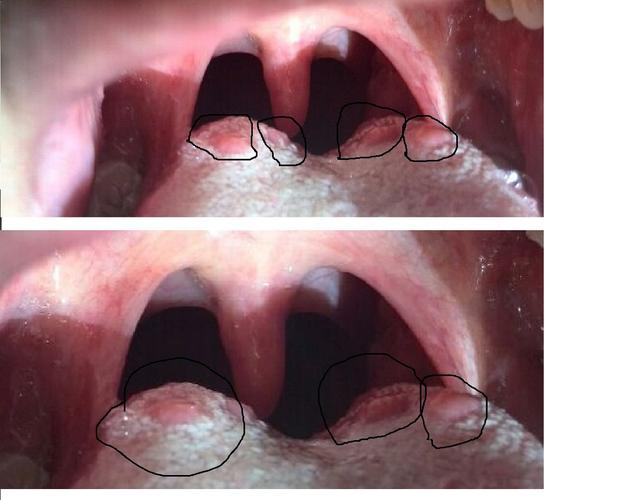

发现舌根部有许多这样的大疙瘩好久了看起来好像尖锐湿疣啊是

舌头里面,舌根处长了很多小疙瘩,是怎么回事?

舌根上有凸起疙瘩图片

舌根有疙瘩图片

舌根两侧有疙瘩图片

正常人舌根有疙瘩图片

舌根滤泡增生图片

舌根淋巴滤泡增生图片